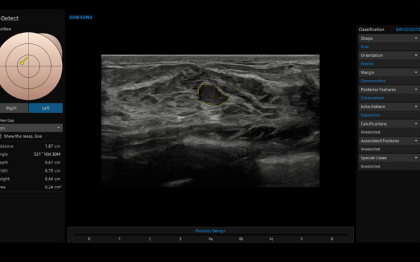

V7 GI

V7 GI – Ecógrafo para Diagnóstico General

El ecógrafo Samsung V7 GI está diseñado para ofrecer diagnósticos de alta precisión en aplicaciones generales, incluyendo abdomen, pediatría, vascular, urología y musculoesquelético. Combina Crystal Architecture™ con funciones inteligentes que aceleran el flujo de trabajo y permiten obtener resultados consistentes y confiables. Su diseño ergonómico y su interfaz intuitiva facilitan la práctica diaria de profesionales sanitarios en hospitales, clínicas generales y estudios especializados.

Aplicaciones principales: Diagnóstico abdominal, estudios pediátricos, evaluación vascular, exploración musculoesquelética, ultrasonido ginecológico y urológico.

HQ-Vision

Esta función permite la clasificación de tumores ováricos según un modelo internacional reconocido, aumentando significativamente la precisión diagnóstica. IOTA-ADNEX™ ayuda a los profesionales a identificar riesgos potenciales y planificar el manejo clínico de manera más segura, proporcionando información fiable para decisiones médicas críticas.